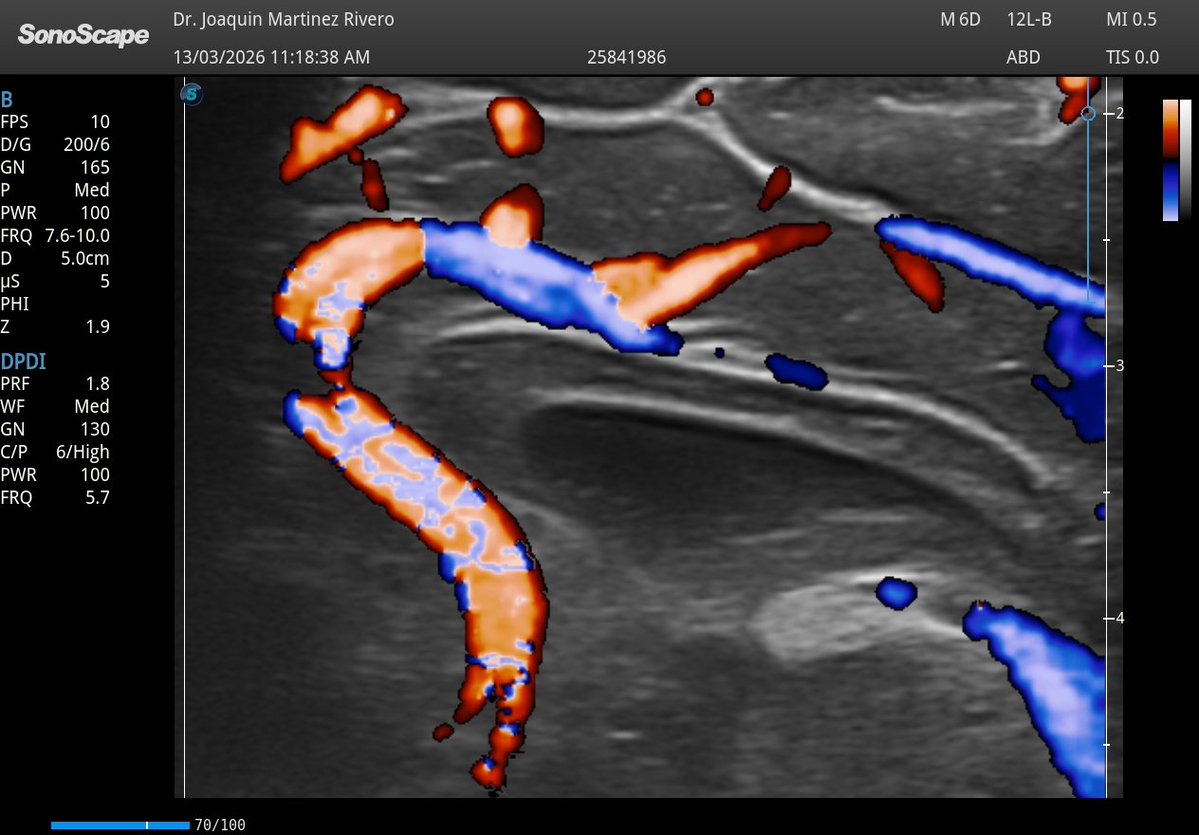

Una de las cosas que más he notado con la mejora de nuestro equipo es la calidad del doppler, ¡qué diferencia!